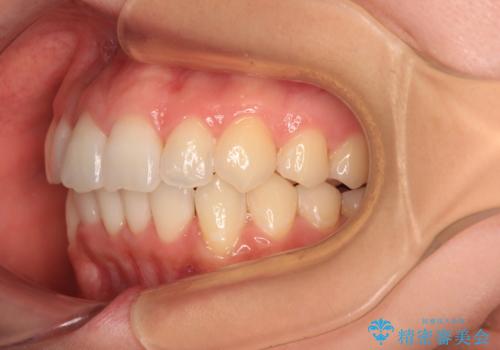

- 前歯のデコボコで前方に出ていることを気にして来院された患者様です。

上顎前歯が捻れて前方に飛び出しており、下顎前歯もそれに沿うようにデコボコとなっていました。

IPR(歯と歯の間を削る処置)によりスペースを獲得して上下顎前歯のデコボコを改善し、飛び出している前歯が引っ込むように設定し、インビザラインにて矯正治療を行うこととしました。